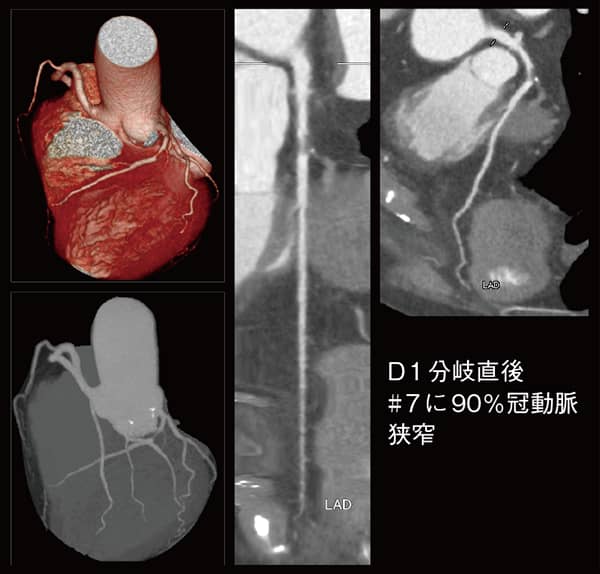

他社製16列CTの更新がきっかけだったが、冠動脈CT検査が可能な装置として機種選定を行い、Aquilion Serveが選定された。藤井部長は、「以前の所属先でキヤノンメディカルシステムズの装置で冠動脈CT検査を経験しており、冠動脈の描出能の高さは評価していました。不整脈や高心拍患者への対応など冠動脈CT検査のための機能や、画質、操作性などをトータルに判断して選定しました」と言う。虚血性心疾患に対する冠動脈CT検査の位置づけについて藤井部長は、「80列CT導入以前は、胸痛などの症状や運動負荷心電図の所見を基に冠動脈造影検査の適応を判断していました。しかし、運動負荷心電図は検出率が低く、冠動脈造影検査が無駄になったり、診断までに時間がかかったりということがありました。冠動脈CT検査は、心エコー検査で原因診断のつかない心不全患者や糖尿病や高血圧などの動脈硬化の多重リスク患者に行い、その所見を基に冠動脈造影検査を行うことで、心筋虚血が速やかに診断でき治療につながるようになりました」と述べる。

Aquilion Serveは、ディープラーニングを用いて設計された画像再構成技術「Advanced intelligent Clear-IQ Engineintegrated(AiCE-i)」による高画質・低被ばく検査と、「INSTINX」と呼ばれる自動化技術でワークフローを支援する80列CTである。冠動脈CT検査は、毎週水曜日の13時半から午後の外来が始まる15時までに3枠が設定されている。検査に当たっては藤井部長のほか、看護師、診療放射線技師が立ち会い、造影剤のルート確保やβ遮断薬の投与などの前処置から検査終了までを行う。冠動脈の解析には、医用画像処理ワークステーション「AZE VirtualPlace」を使用している。冠動脈CT検査の運用に関してはゼロからのスタートだったが、特にトラブルもなく順調に立ち上がった。これまで150件を施行しているが村上放射線科部長は、「撮影プロトコールや検査フローを含めて、キヤノンメディカルシステムズのサポートもあり、スムーズに立ち上げることができました」と述べる。同院の冠動脈CT検査は、1回の造影剤投与で冠動脈のみ、冠動脈+大動脈、冠動脈+下肢動脈の造影検査を行っている。藤井部長は、「これらは患者さんの症状や病態によって選択しています。糖尿病患者では、虚血性心疾患と末梢動脈疾患の合併はしばしばあり、間欠性跛行患者に冠動脈病変が見つかることもあります」と述べる。

Aquilion Serveについて藤井部長は、「撮影時間が短く、長い息止めが難しい高齢者でも検査が可能です。また、心房細動の患者でも心拍をコントロールすることで診断が可能な画像が得られています」と評価する。通彦医師は、「Aquilion Serveでは、冠動脈が明瞭に描出され評価がしやすくなりました。患者さんへの説明も画像を提示することで狭窄や閉塞の有無が一目でわかり、理解を得やすくなりました。これによって患者側の負担も医師の負担も軽減されており、大きなメリットを感じています」と述べる。冠動脈造影検査の実施件数は冠動脈CT導入以前より増えている。藤井部長は、「この地域にはまだ潜在的な動脈硬化性の心不全患者が多く、CTによってそれらを的確に拾い上げることができているからだと思います」と言う。